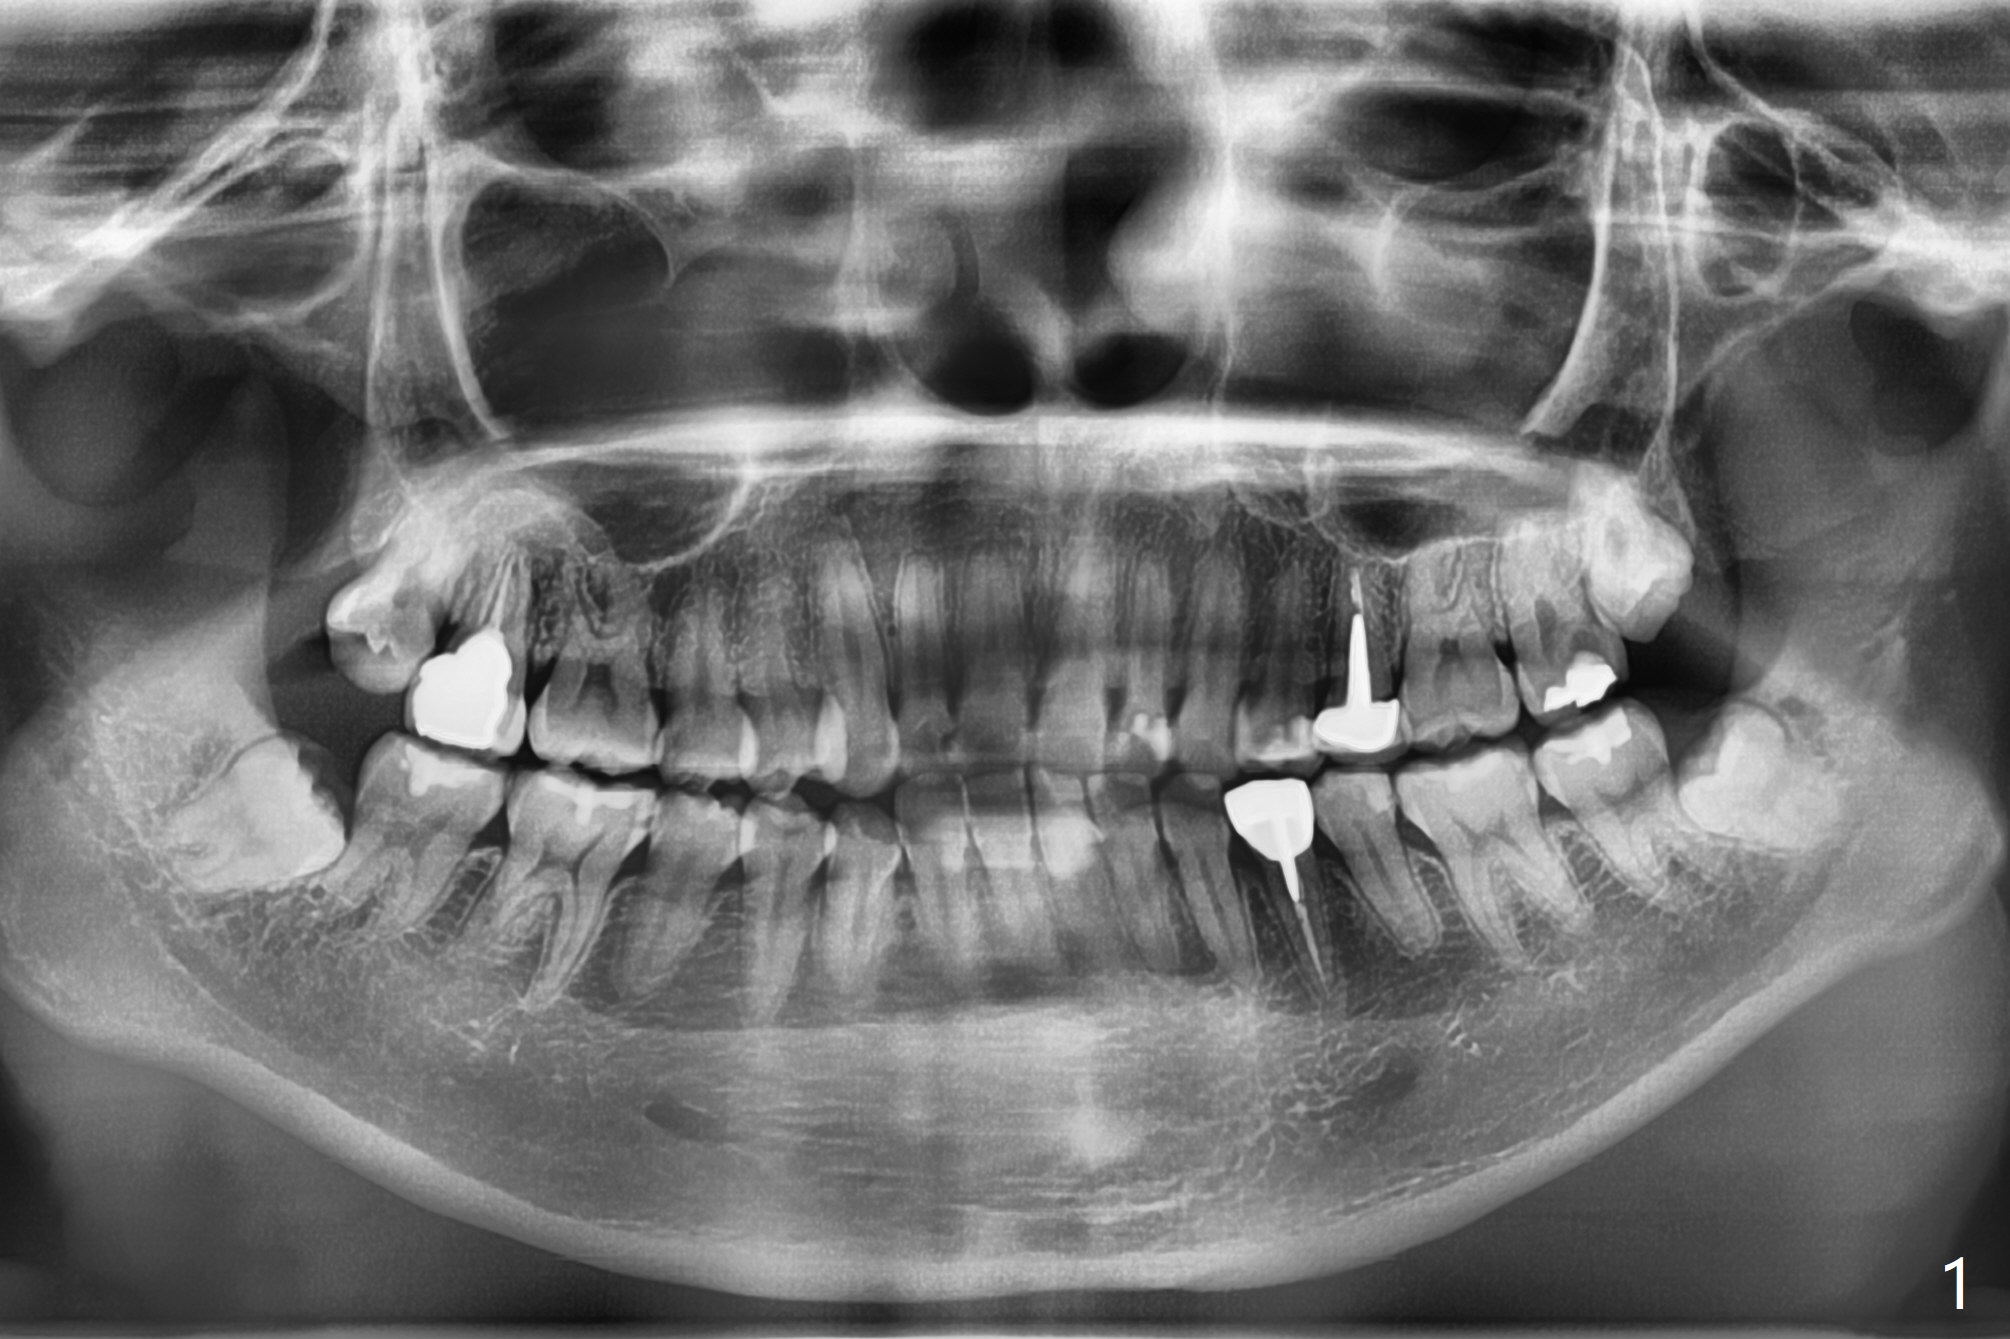

拔牙与挖匙

26岁女要求拔除右上8(图一),我们外科拔牙盒里有三个宽度不同刮匙(图二),最好刮匙炳要长的,太短,牙根长,根尖病变,深部肉芽组织无法清除。去除肉芽组织另外一个锐利武器是血管钳,必须新,大小两个,不能用于夹硬组织。